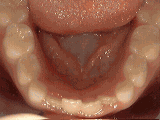

Openbite: Front teeth don't touch

openbite

Patient sucked her thumb as a young child. She started treatment at age thirteen. She had braces and a special appliance — called a crib — to retrain the tongue, for twenty-eight months. Now she can bite the lettuce out of a sandwich.